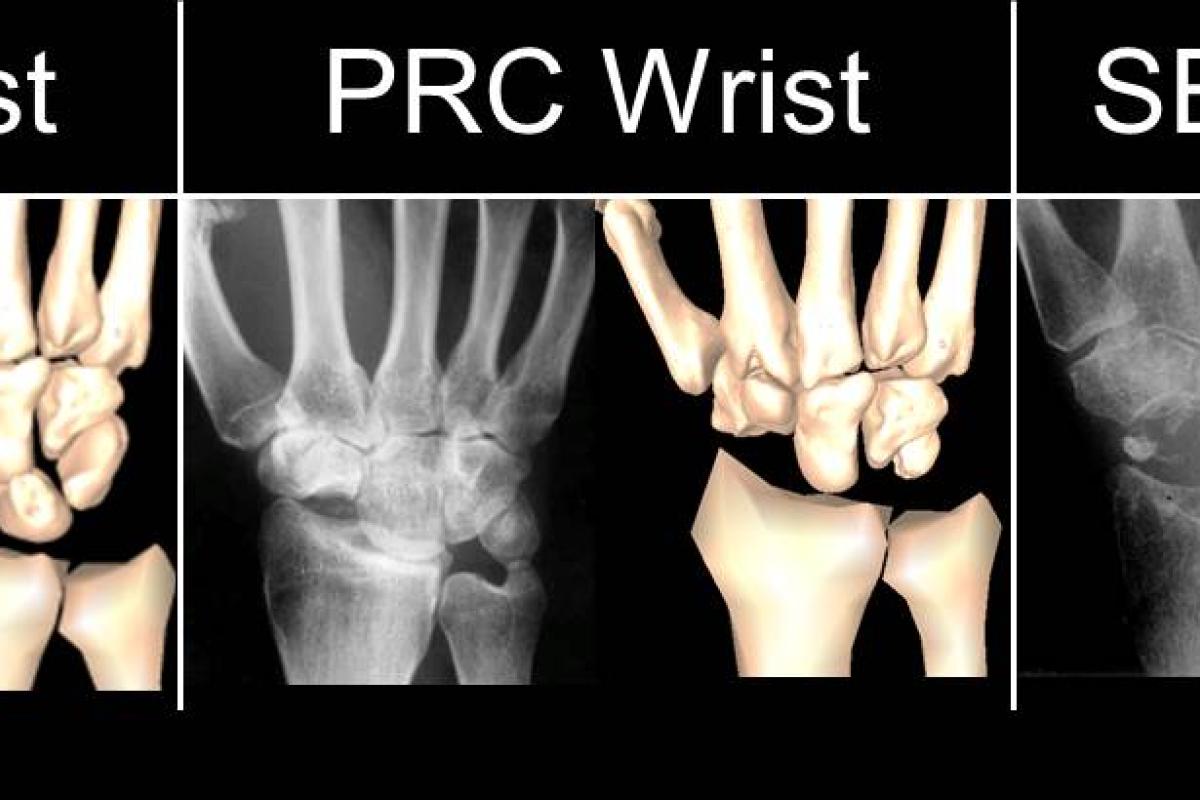

From www.sralab.org

How do wrist surgical salvage procedures limit hand strength? Heat After Wrist Surgery This leaflet is designed to guide you through the recovery process after your recent operation. Web “ crunches or clicks in the fingers are another warning sign that may appear after surgery, especially in the. Web wrist surgery can be done to fix problems like arthritis, fractures, and carpal tunnel. Web it is recommended that you exercise your wrist as. Heat After Wrist Surgery.